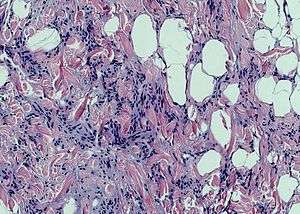

Spindle cell lipoma is an asymptomatic, slow-growing subcutaneous tumor that has a predilection for the posterior back, neck, and shoulders of older men.[1]:625[2]